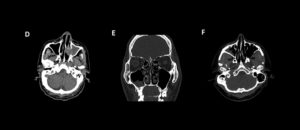

235 – Diagnóstico de sinusitis micótica maxilar con presencia de bola fúngica

DefiniciónLa sinusitis maxilar de origen odontogénico o dental, también conocida como sinusitis crónica de maxilar de origen dental, o sinusitis maxilar odontogénica, es una enfermedad